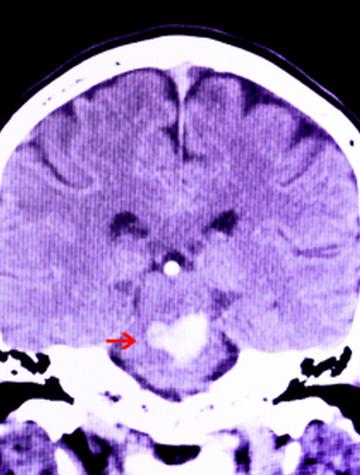

L’acide tranexamique après une hémorragie cérébrale, à administrer plus tôt ?

Le pronostic des hémorragies intracrâniennes est grevé par une mortalité élevée (40 % après 1 mois) mais aussi par des séquelles handicapantes [...]